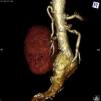

Presentamos el caso de un paciente que presenta como hallazgo casual, en una TC, un aneurisma de aorta infrarrenal y una interesante variante anatómica, consistente en una arterial renal derecha redundante, y con origen proximal al tronco celíaco (figs. 1 y 2).

DiagnósticoArteria renal derecha con origen aberrante.